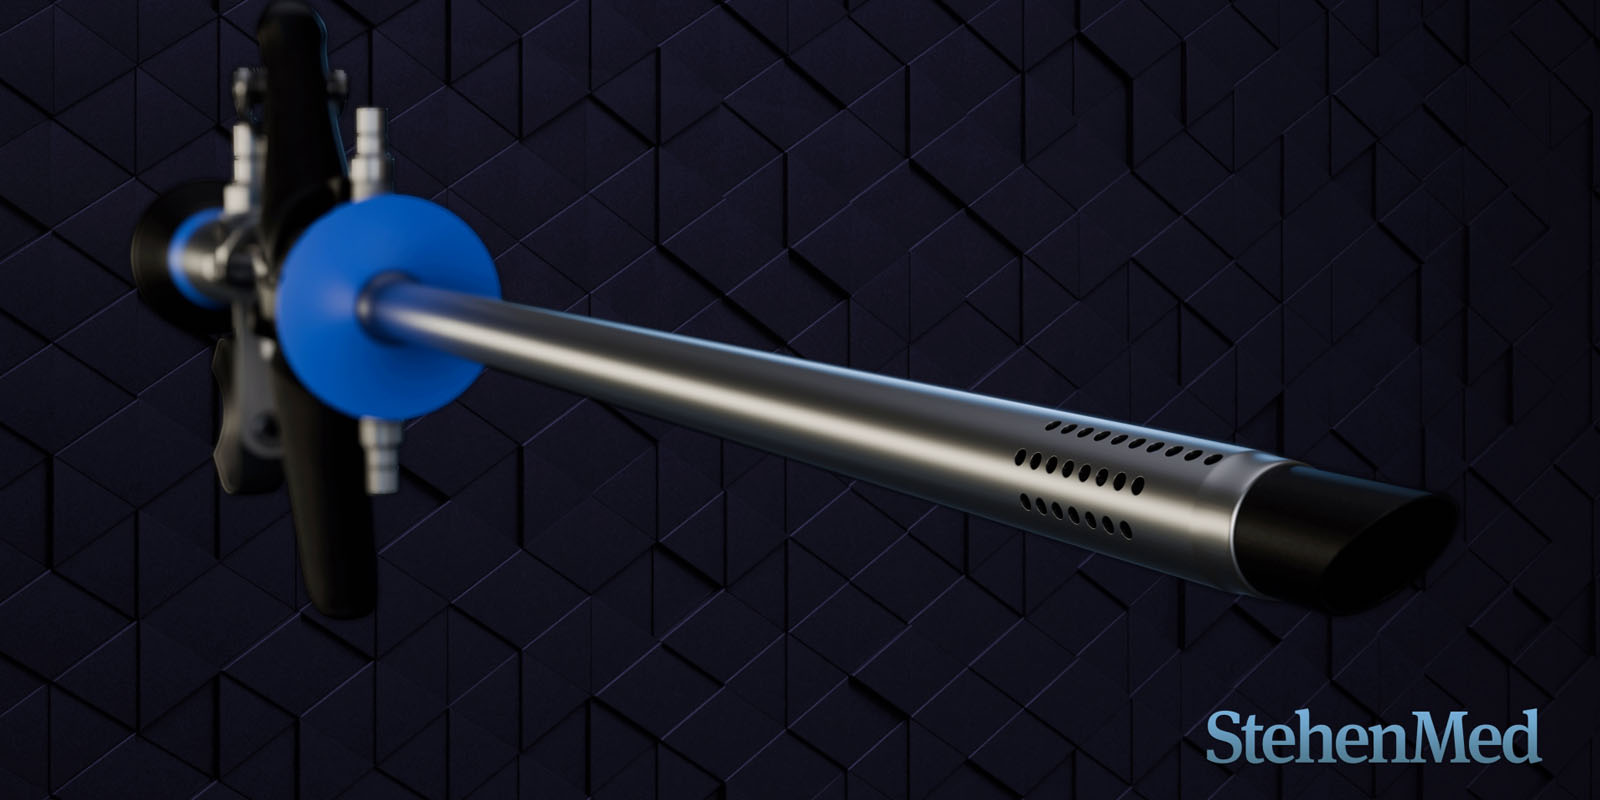

Modelado 3D de un Resectoscopio del tipo Activo

Categoría: Animación 3D - Render Producto

Conceptos clave: Render, Resectoscopio, Producto

Duración: 1m 15s